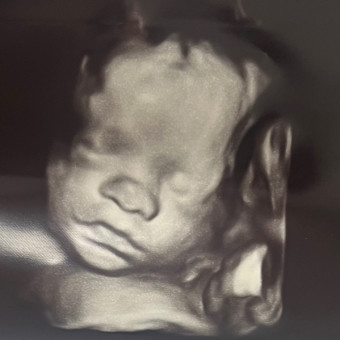

Smith Baby #2

We are so excited to celebrate and welcome our sweet girl 💕🎀